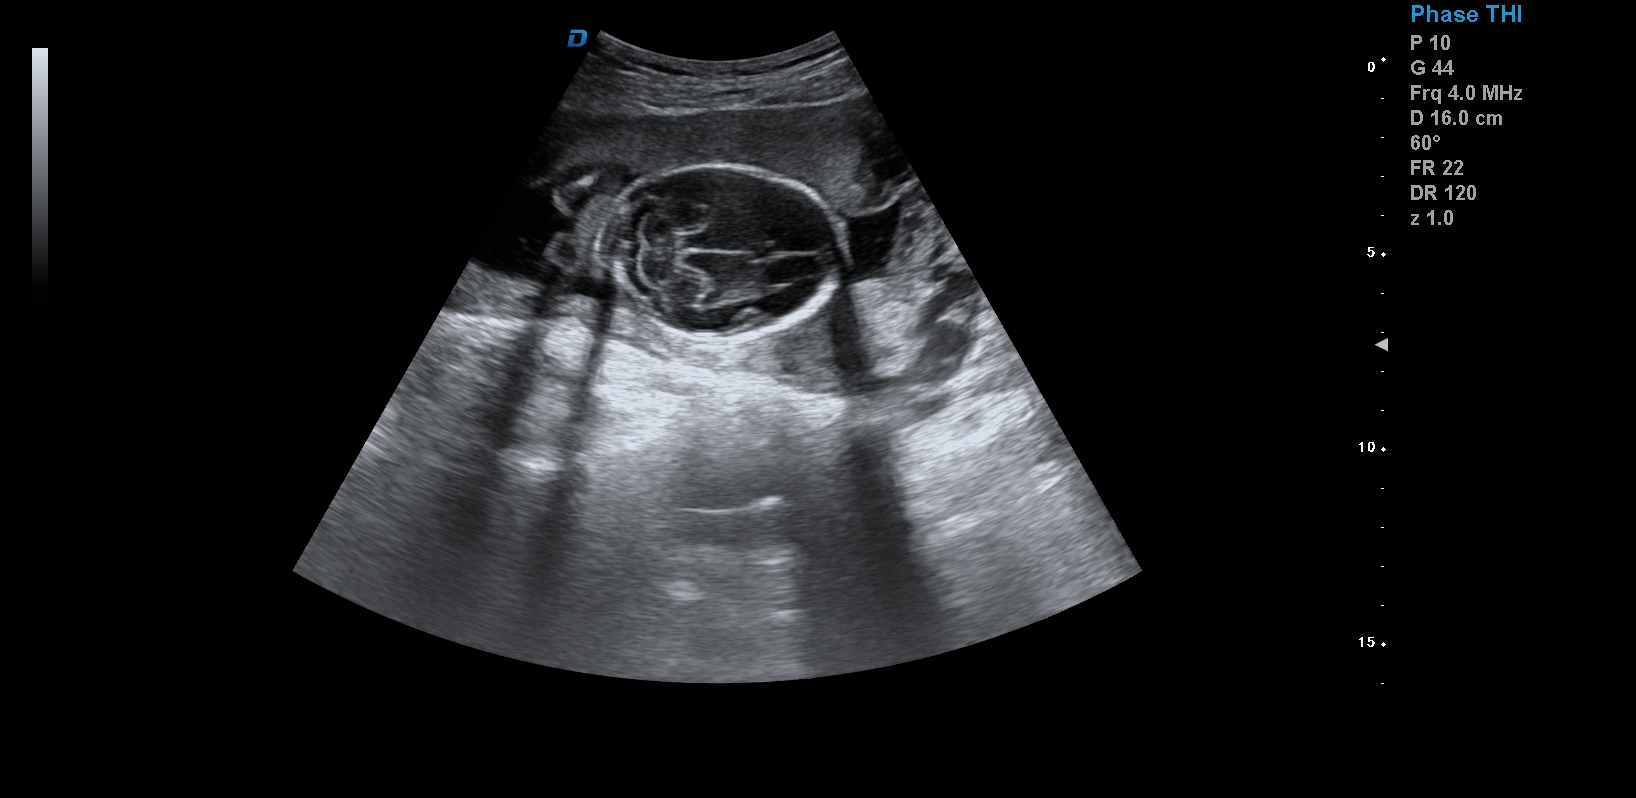

首先,四維彩超檢查是采用高清晰度的彩超儀對胎兒進行各個心臟器官及組織的一次全面檢查,可以立體顯示胎兒的發(fā)育情況,胎兒在子宮內(nèi)的任何狀態(tài)都可以觀察到。對胎兒畸形能夠早診斷,及時地做出相應的措施,以達到優(yōu)生優(yōu)育的標準。

四維彩超不但成像清晰,更是在三維的基礎(chǔ)之上附加時間這個矢量。這就在排畸的同時能時刻觀察寶寶在宮內(nèi)的一舉一動,吃手指、打哈欠、吮吸……寶寶在宮內(nèi)憨態(tài)可掬,讓孕媽媽母愛井噴,幸福不已。這也是孕媽媽們選擇四維的主要原因,試想,誰不想在辛苦懷孕期間提前看一看自己寶寶的模樣呢?

1、四維彩超是目前先進的彩色超聲技術(shù).能直觀立體現(xiàn)實人體器官動靜態(tài)三維結(jié)構(gòu),一定程度上提高臨床診斷的準確性。

3、清晰成像:采用先進的超聲成像技術(shù),擁有高清晰,高分辨率、高精確度優(yōu)點,能清晰看到包括生殖器、內(nèi)臟器官在內(nèi)的胎兒的各個部位發(fā)育情況.